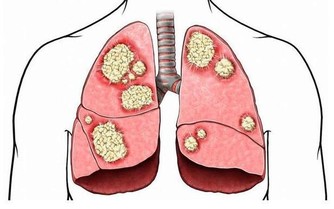

部分研究指出,定期捐血與降低某些癌症(如肝癌與肺癌)風險之間存在一定關聯,特別是體內鐵含量偏高者。